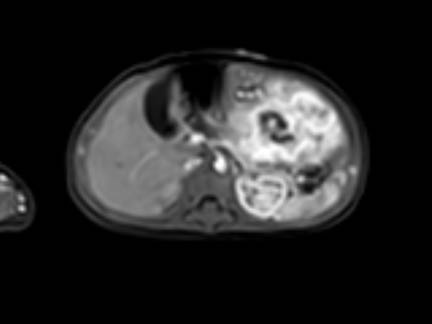

Hình ảnh MRI của một bé gái chín tháng tuổi có khối u ở bụng trái. MRI cho thấy khối u tuyến thượng thận trái, một phần đặc, một phần nang. Có nhiều di căn gan.

Khối u đã được sinh thiết. Có tình trạng chảy máu liên tục qua kim dẫn đường. Vào cuối thủ thuật, hai nút bọt gelatin đã được đặt vào (các dải tăng âm (mũi tên)).